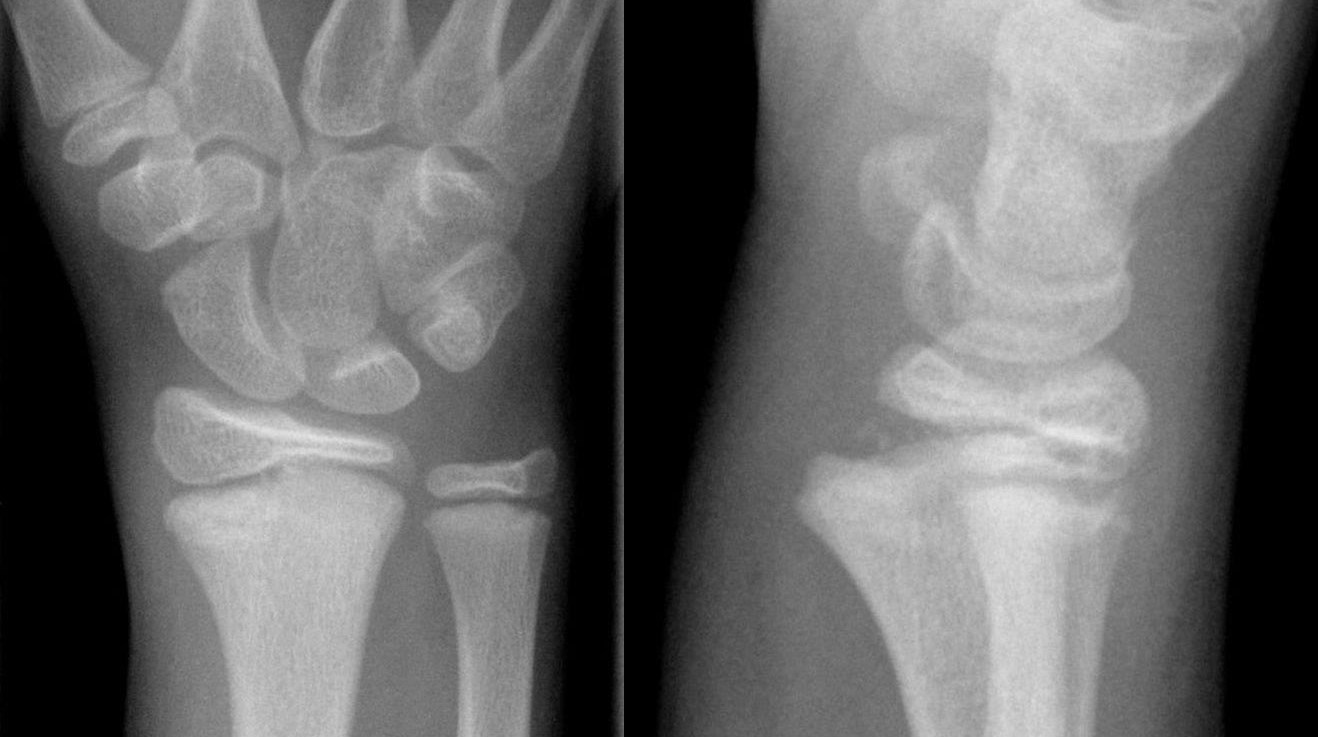

Subcapitulär metacarpalfraktur

Subcapitulär metacarpalfraktur är en vanlig slagsmålsskada och drabbar då ofta metacarpale V. Frakturen dislocerar alltid volart och viss kvarvarande volarställning (ca 30-40° i MCP V) kan accepteras. Behandlas annars med sluten reposition och gips i 3 veckor.